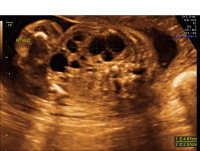

Multicystic Dysplastic Kidney (MCDK)

Multicystic dysplastic kidneys (MCDK) occur when one (unilateral) or both (bilateral) kidneys do not develop properly. During formation, the kidney(s) becomes filled with multiple cysts that make it non-functional. MCDK occurs in one out of 1,000 to 5,000 births, with more frequency in males.

Multicystic dysplastic kidney